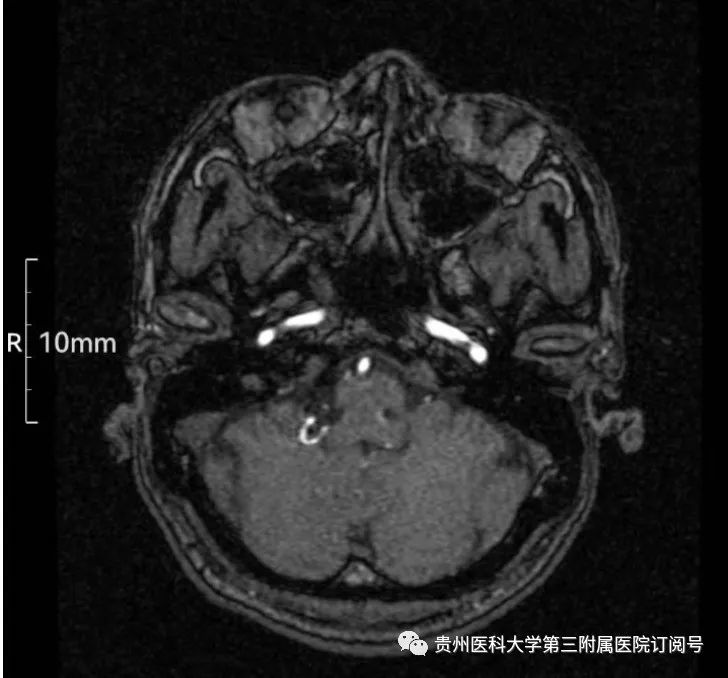

我院神经外科副主任、主任医师王勇带领科室团队对患者进行详细问诊、查体、检查,诊断为舌咽神经痛。由于颅内一条重要的神经受相邻血管压迫,在充分评估患者病情后,决定为韦叔叔在显微镜下实施舌咽神经微血管减压术。